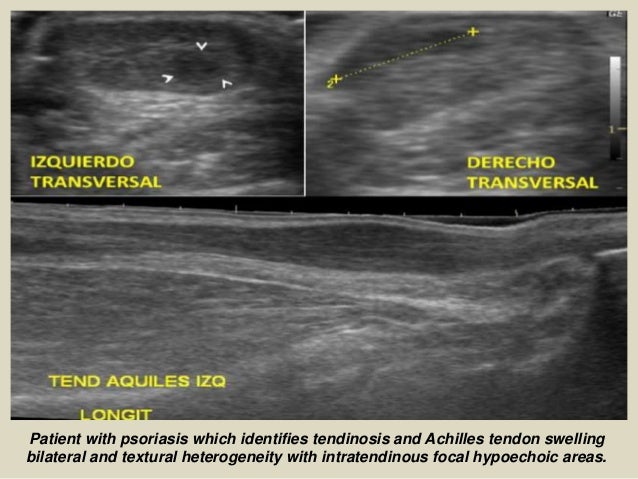

Patient with psoriasis which identifies tendinosis and Achilles tendon swelling

bilateral and textural heterogeneity with ...

21. 21. Patient with psoriasis which identifies tendinosis and Achilles tendon swelling bilateral and textural heterogeneity with intratendinous focal hypoechoic areas.